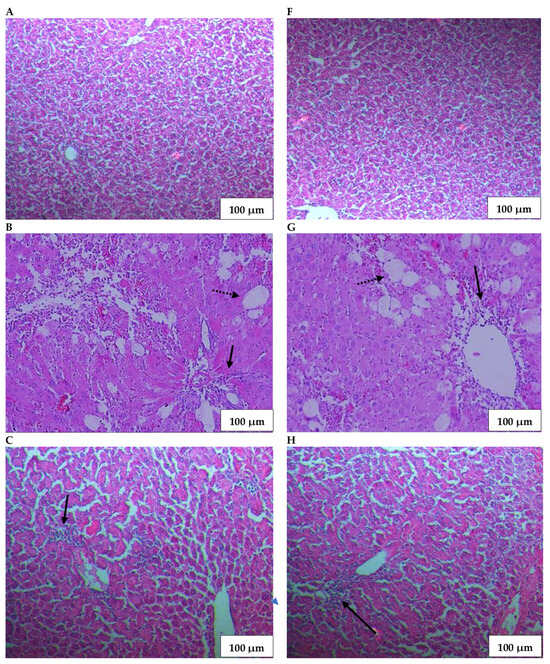

Expectedly, CCl4 activated the resident macrophages of the liver (Figure 3B,G). These cells, also known as Kupffer cells, produce chemo-attractants which activate and recruit neutrophils into the site of liver damage [16]. Furthermore, neutrophils release ROS and cause inflammation and alteration in the structure of the hepatocytes, leading to hepatotoxicity [46]. Accordingly, histological examination revealed inflammatory cell infiltrate and centrilobular necrosis of the hepatocytes as the predominant features of the group treated by CCl4 only. Additionally, the proliferation of fibrous tissue between portal spaces was also seen. Animals that received A. tomentosum therapy showed an improvement in the liver’s histological structure. The down-regulation of the inflammatory reaction was slightly visible at the dose of 200 mg/kg (Figure 3D,I); however, the improvement was more evident at the dose of 400 mg/kg (Figure 3E,J) administered for both four and six weeks. Overall, the alleviation of the hepatocyte necrosis as well as the fibrosis process was mainly seen at the dose of 400 mg/kg, while the benefits in the case of the groups receiving the doses of 50 and 200 mg/kg were minimal.

Figure 3.

Effects of A. tomentosum subcritical fluid-assisted root extract on the histologic aspect of the liver: (A,F) the negative control group; (B,G) the positive control group receiving only carbon tetrachloride (1 mL/b.w.) showed inflammatory infiltrate (black arrow) and hepatocyte necrosis (doted black arrow); groups receiving therapy with the extract in a dose of (C,H) 50 mg/b.w.; (D,I) 200 mg/b.w.; and (E,J) 400 mg/b.w. Duration: (A–E) four weeks; (F–J) six weeks. Hematoxylin and Eosin stain; Bar, 100 μm.